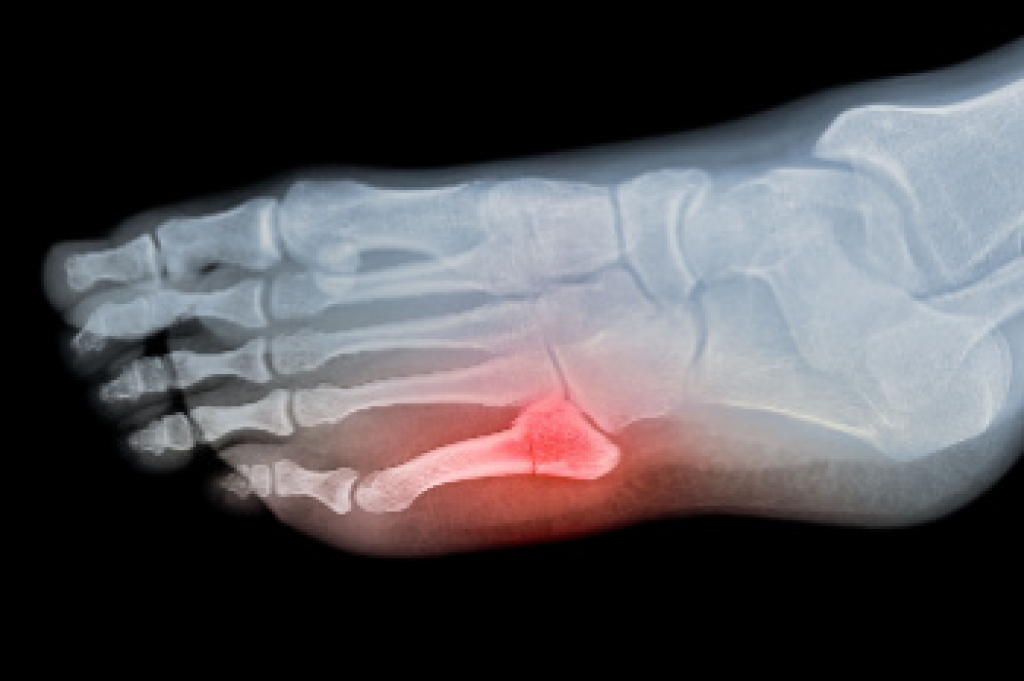

Broken Toes and Podiatric Care

A broken toe is a fracture of one or more of the small bones in the toe, often resulting from sudden trauma. Common causes include a heavy object falling on the foot, or forceful stubbing against furniture or hard surfaces. Symptoms usually involve pain, swelling, bruising, and difficulty walking. Discolored toenails may appear when bleeding occurs beneath the nail. Diagnosis is typically made through a physical exam and imaging, such as X-rays, to confirm the fracture and its severity. Risk factors include sports activities, poor footwear protection, and balance issues. If you have symptoms of a broken toe, it is suggested that you promptly consult a podiatrist who can provide an accurate diagnosis, stabilize the toe, manage pain, and guide proper healing.

Broken toes may cause a lot of pain and should be treated as soon as possible. If you have any concerns about your feet, contact one of our podiatrists from Dr. Jeffrey J. Betman & Associates . Our doctors will treat your foot and ankle needs.

What Is a Broken Toe?

A broken toe occurs when one or more of the toe bones of the foot are broken after an injury. Injuries such as stubbing your toe or dropping a heavy object on it may cause a toe fracture.